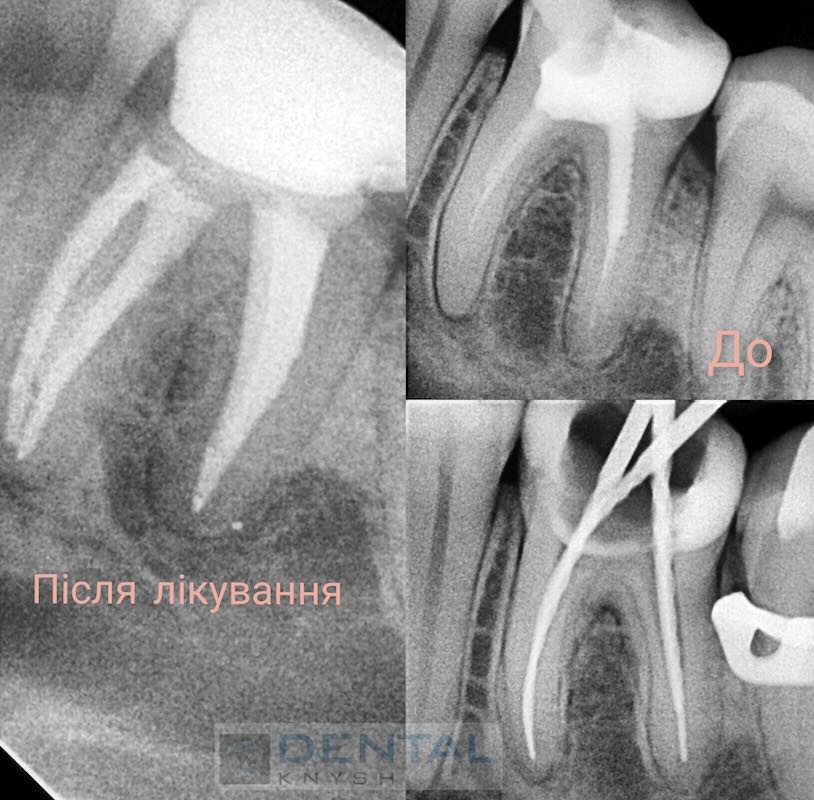

„Leczenie kanałowe pod mikroskopem daje najlepsze wyniki leczenia bez żadnych zastrzeżeń.

Nie każda klinika ma mikroskop do leczenia stomatologicznego, ale w przyszłości mikroskop będzie koniecznością. Im lepszy widok pola pracy, tym lepsze wyniki leczenia.

Początkowo fotele dentystyczne były w tym celu uzupełniane lampami, ale wraz z pojawieniem się mikroskopów stomatologia weszła w nowy etap rozwoju”.

Fotorelacje